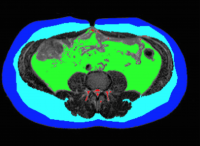

In obese mice, a liver enzyme travels to visceral fat and increases inflammation (inflammatory cells labeled red), thereby promoting diabetes filled with cells. The photo on the right shows fat tissue from obese mice who have been given a drug that blocks the enzyme. Images: Ira Tabas / Columbia University Irving Medical Center

The good news is that this inflammation can be soothed by turning off DPP4 production in the liver, as the researchers demonstrated in mice. And even though the animals remained obese, soothing inflamed abdominal fat improved their insulin resistance.

When the researchers selectively blocked DPP4 production inside liver cells, they were able to reduce fat inflammation and improve insulin resistance, while also lowering blood sugar.